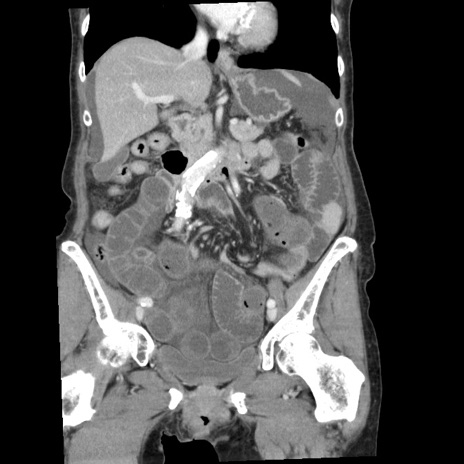

症例1(冠状断像)

【症例】80歳代女性

【主訴】腹痛

【現病歴】8時間前から腹痛あり来院。

【既往歴】糖尿病、脂質異常症、子宮体癌にて子宮全摘術

【身体所見】意識清明・会話良好だが腹痛で苦悶様、全腹部にわたって反跳痛と圧痛あり

【データ】WBC 13600、CRP 0.14、LDH 224、CK 90

横断像